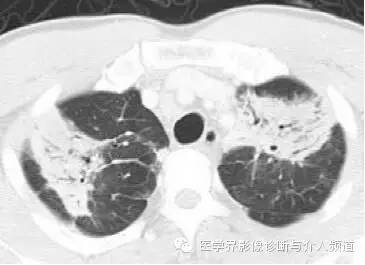

初始CT

初始胸片示两肺野多灶性斑片影,其中两肺上野靠近外周可见边界欠清的实变影,这是典型的慢性嗜酸性粒细胞性肺炎“肺水肿反转影”的表现。CT示两肺叶多灶性非节段性实变影,病变以两上肺周围性分布为主。

CEP的典型影像学表现:普通X线平片为非节段性、分布广泛互相融合的肺泡及间质性实变,病变以中上肺周围性分布为主,表现为“肺水肿反转影”。CT或HRCT表现为一侧或两侧融合性实变、斑片状实变、磨玻璃影、条带状致密影,实变灶与正常肺组织的分界截然清楚。此种典型征象并非见于所有CEP病例。